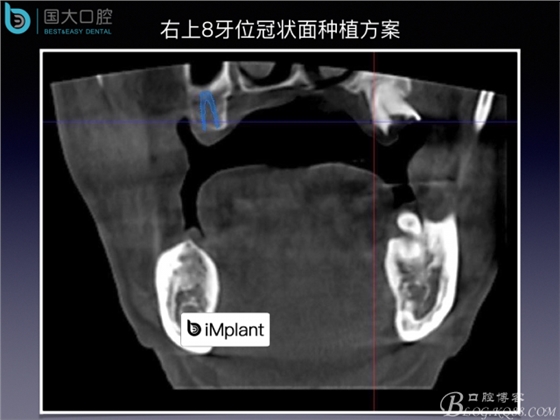

上頜竇底區(qū)域嚴(yán)重骨吸收的臨床種植案例